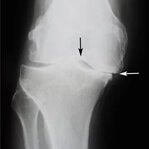

Osteoartrita distruge treptat țesutul cartilaginos și duce la deformarea articulațiilor. În timp, chiar și cele mai simple mișcări devin imposibile, iar durerea devine constantă. O terapie corectă ajută la încetinirea progresiei bolii.